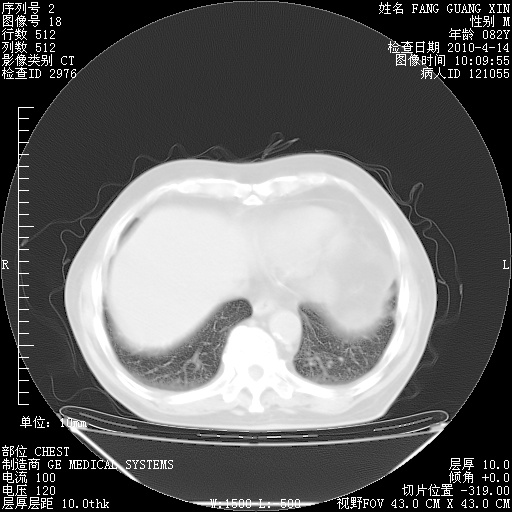

肺部CT平扫未见异常。